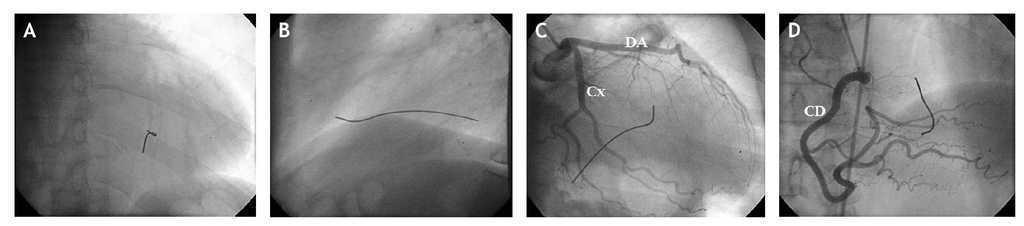

Durante la angiografía no contrastada se constató, sobre la silueta cardíaca, la presencia de un CE alargado, de aproximadamente 10 cm de longitud, con orientación anteroposterior, localizado a la izquierda y perpendicular a la columna vertebral (fig. 1A y B).

Figura 1 A: angiografía no contrastada. Vista anteroposterior. B: vista lateral. C: coronaria izquierda sin lesiones en vista oblicua anterior derecha con angulación caudal. D: coronaria derecha sin lesiones en vista anteroposterior con angulación craneal. CD: coronaria derecha; Cx: circunfleja; DA: descendente anterior.

Las arterias coronarias eran normales (fig. 1C y D), pero, evidentemente, nos llamó poderosamente la atención que en el expediente clínico no se hiciera alusión a ese hallazgo.